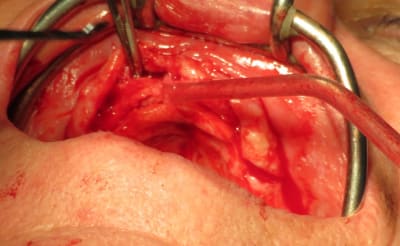

Olieve des crêtes flottantes sont sûrement une contre indication pour une chirurgie guidé flapless mais pas pour un guide à appuis osseux. Un exemple de notre ami béotien sur une patiente édenté total (9) après plusieurs années de port d'une prothèse amovible (10) usée la gencive est flottante. Le guide à appuis osseux a une position stable est précise (11). En fin de chirurgie le bridge à armature métallique rigide est mise en place mettant en charge les implants pour que la patiente retrouver immédiatement la fonction et l'esthétique (13). 8 mois après (14) le bridge est retiré pour vérifier l'ostéo-intégration des implants. La levé du lambeau a permis de positionner favorablement le conjonctif guidé par la prothèse pour la conformée.

Imagine Olieve le même travail avec des implants mis en nourrice puis des vis de cicat prise DV ... le temps nécessaire et l'incertitude du résultat après une mise en charge des implants. Là les tissus sont stabilisés, entre chaque étapes de la réalisation de la prothèse d'usage la prothèse transitoire est replacée. En 1 seule intervention de 3h la patient avait retrouvée un confort de vie.